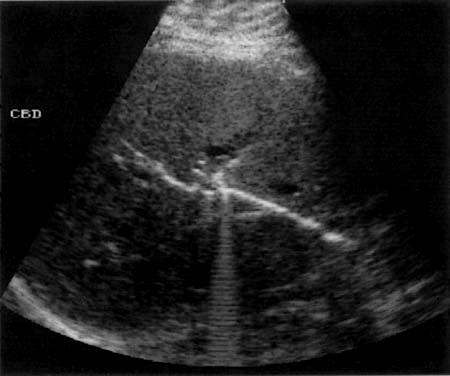

Courvoisier's GB

Distension without wall thickening

due to obstruction distal to the cystic duct

*Panncreatic head mass

* Duodenal papilla mass

*CBD mass